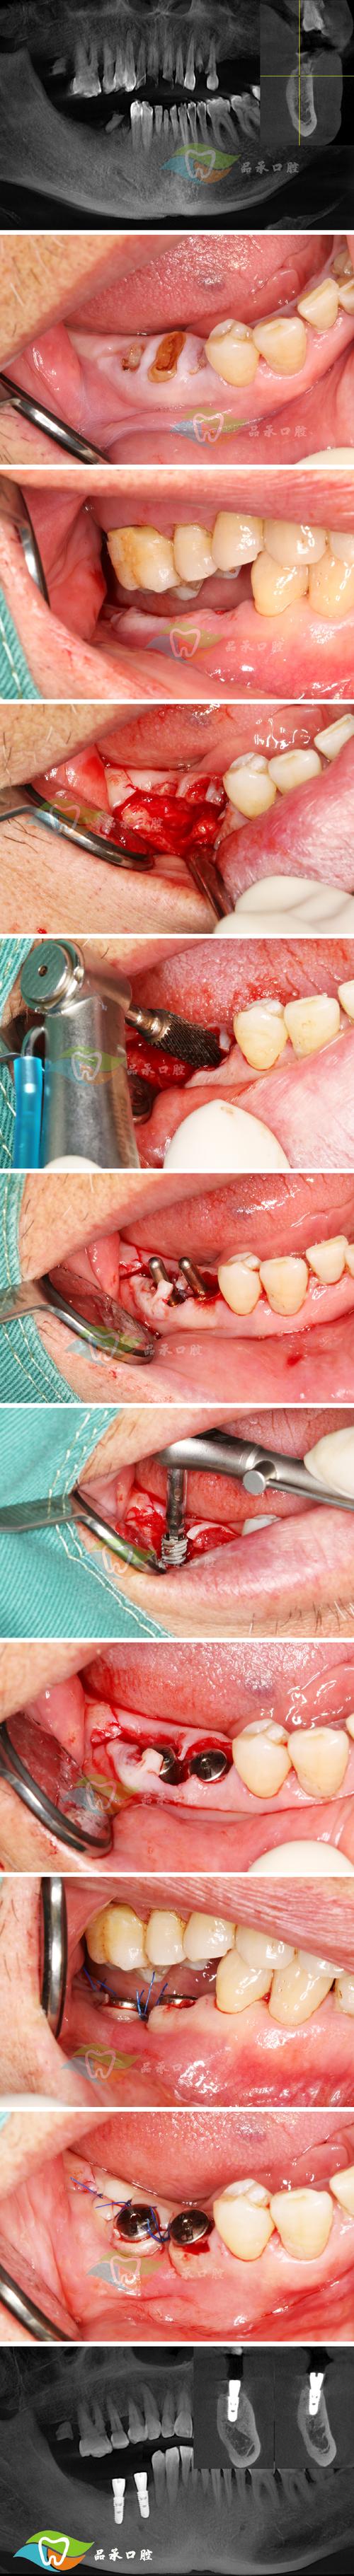

手术阶段:

- 麻醉: 局部麻醉(绝大多数情况)或全身麻醉(复杂病例或患者紧张)。

- 切口: 在缺牙区牙龈上做切口,翻开牙龈瓣,暴露骨缺损区域。

- 植骨: 按照预定方案(如GBR或上颌窦提升),清创骨面,放置骨移植材料,小心放置生物膜(如果是GBR)。

- 缝合: 将牙龈瓣复位,严密缝合伤口。

- (可选)同期种植: 如果骨条件允许且医生计划,可以在植骨的同时植入种植体(称为“同期种植”),如果骨条件差或为了确保骨愈合充分,则先植骨,等骨头长好后再二期手术植入种植体(称为“延期种植”)。

二期手术(如果延期种植):

(图片来源网络,侵删)- 在确认骨愈合良好后,进行二期手术。

- 切开牙龈,暴露埋在骨头里的种植体顶部,安装愈合基台(引导牙龈成形),缝合伤口,等待1-2周后取模。